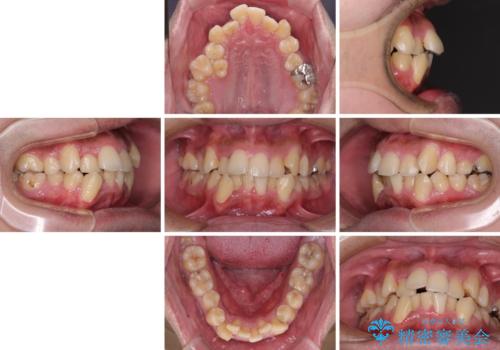

デコボコと口元の突出感を改善 抜歯矯正治療

- 八重歯を気にして来院された患者様です。

上下左右の犬歯が八重歯になっており、口元にもやや突出感があるため、上下左右の小臼歯4本を抜歯し、ワイヤー装置にて矯正治療を行うこととしました。

右上第一小臼歯は歯根癒着により移動せず、左上第二小臼歯は移動はするものの非常に動きが鈍かったため、抜歯したスペースを閉じるまでに非常に時間がかかってしまいました。

患者様には辛抱強く治療にお付き合いいただき、すっきりとした口元に仕上げることができました。